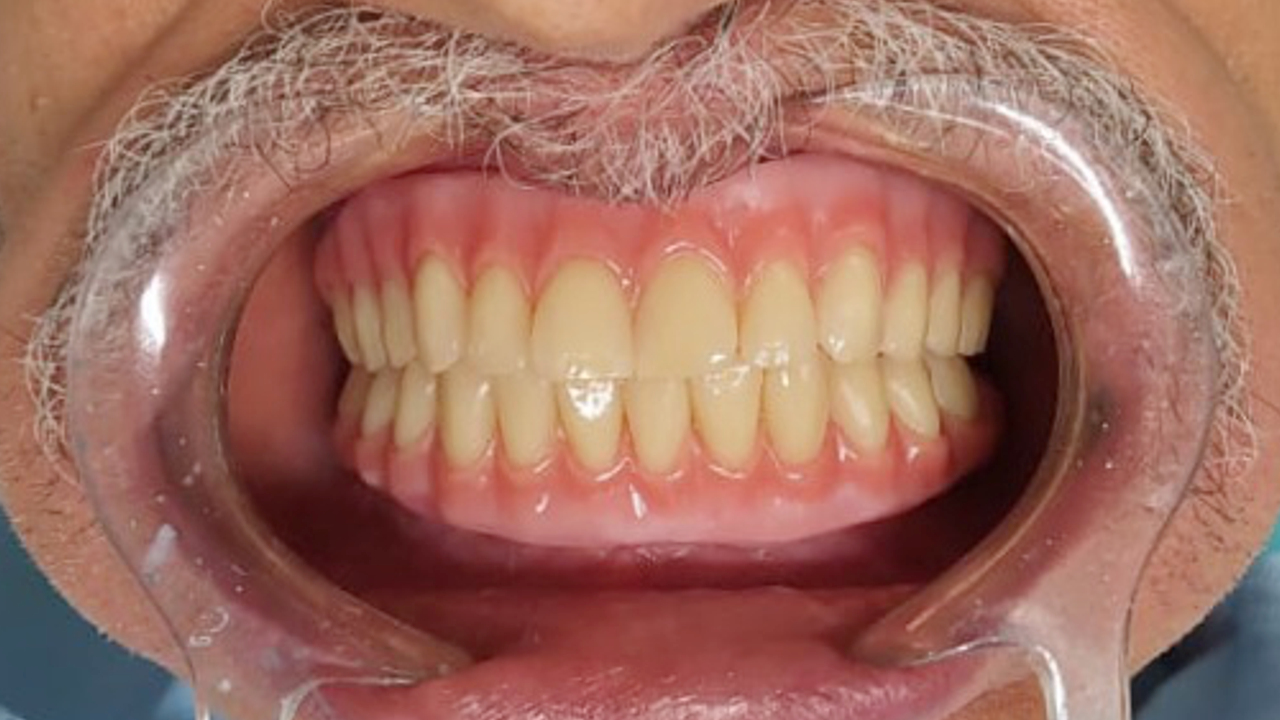

PROTOCOLO é um tipo de prótese que fica presa por implantes, substituindo a dentadura móvel. Ou seja, DISPENSA o uso de pastas ou adesivos fixadores. Só o dentista consegue por e tirar a prótese da sua boca!😷 Além disso, o PROTOCOLO, melhora a mastigação e a fala,

melhorando a qualidade de VIDA dos pacientes.